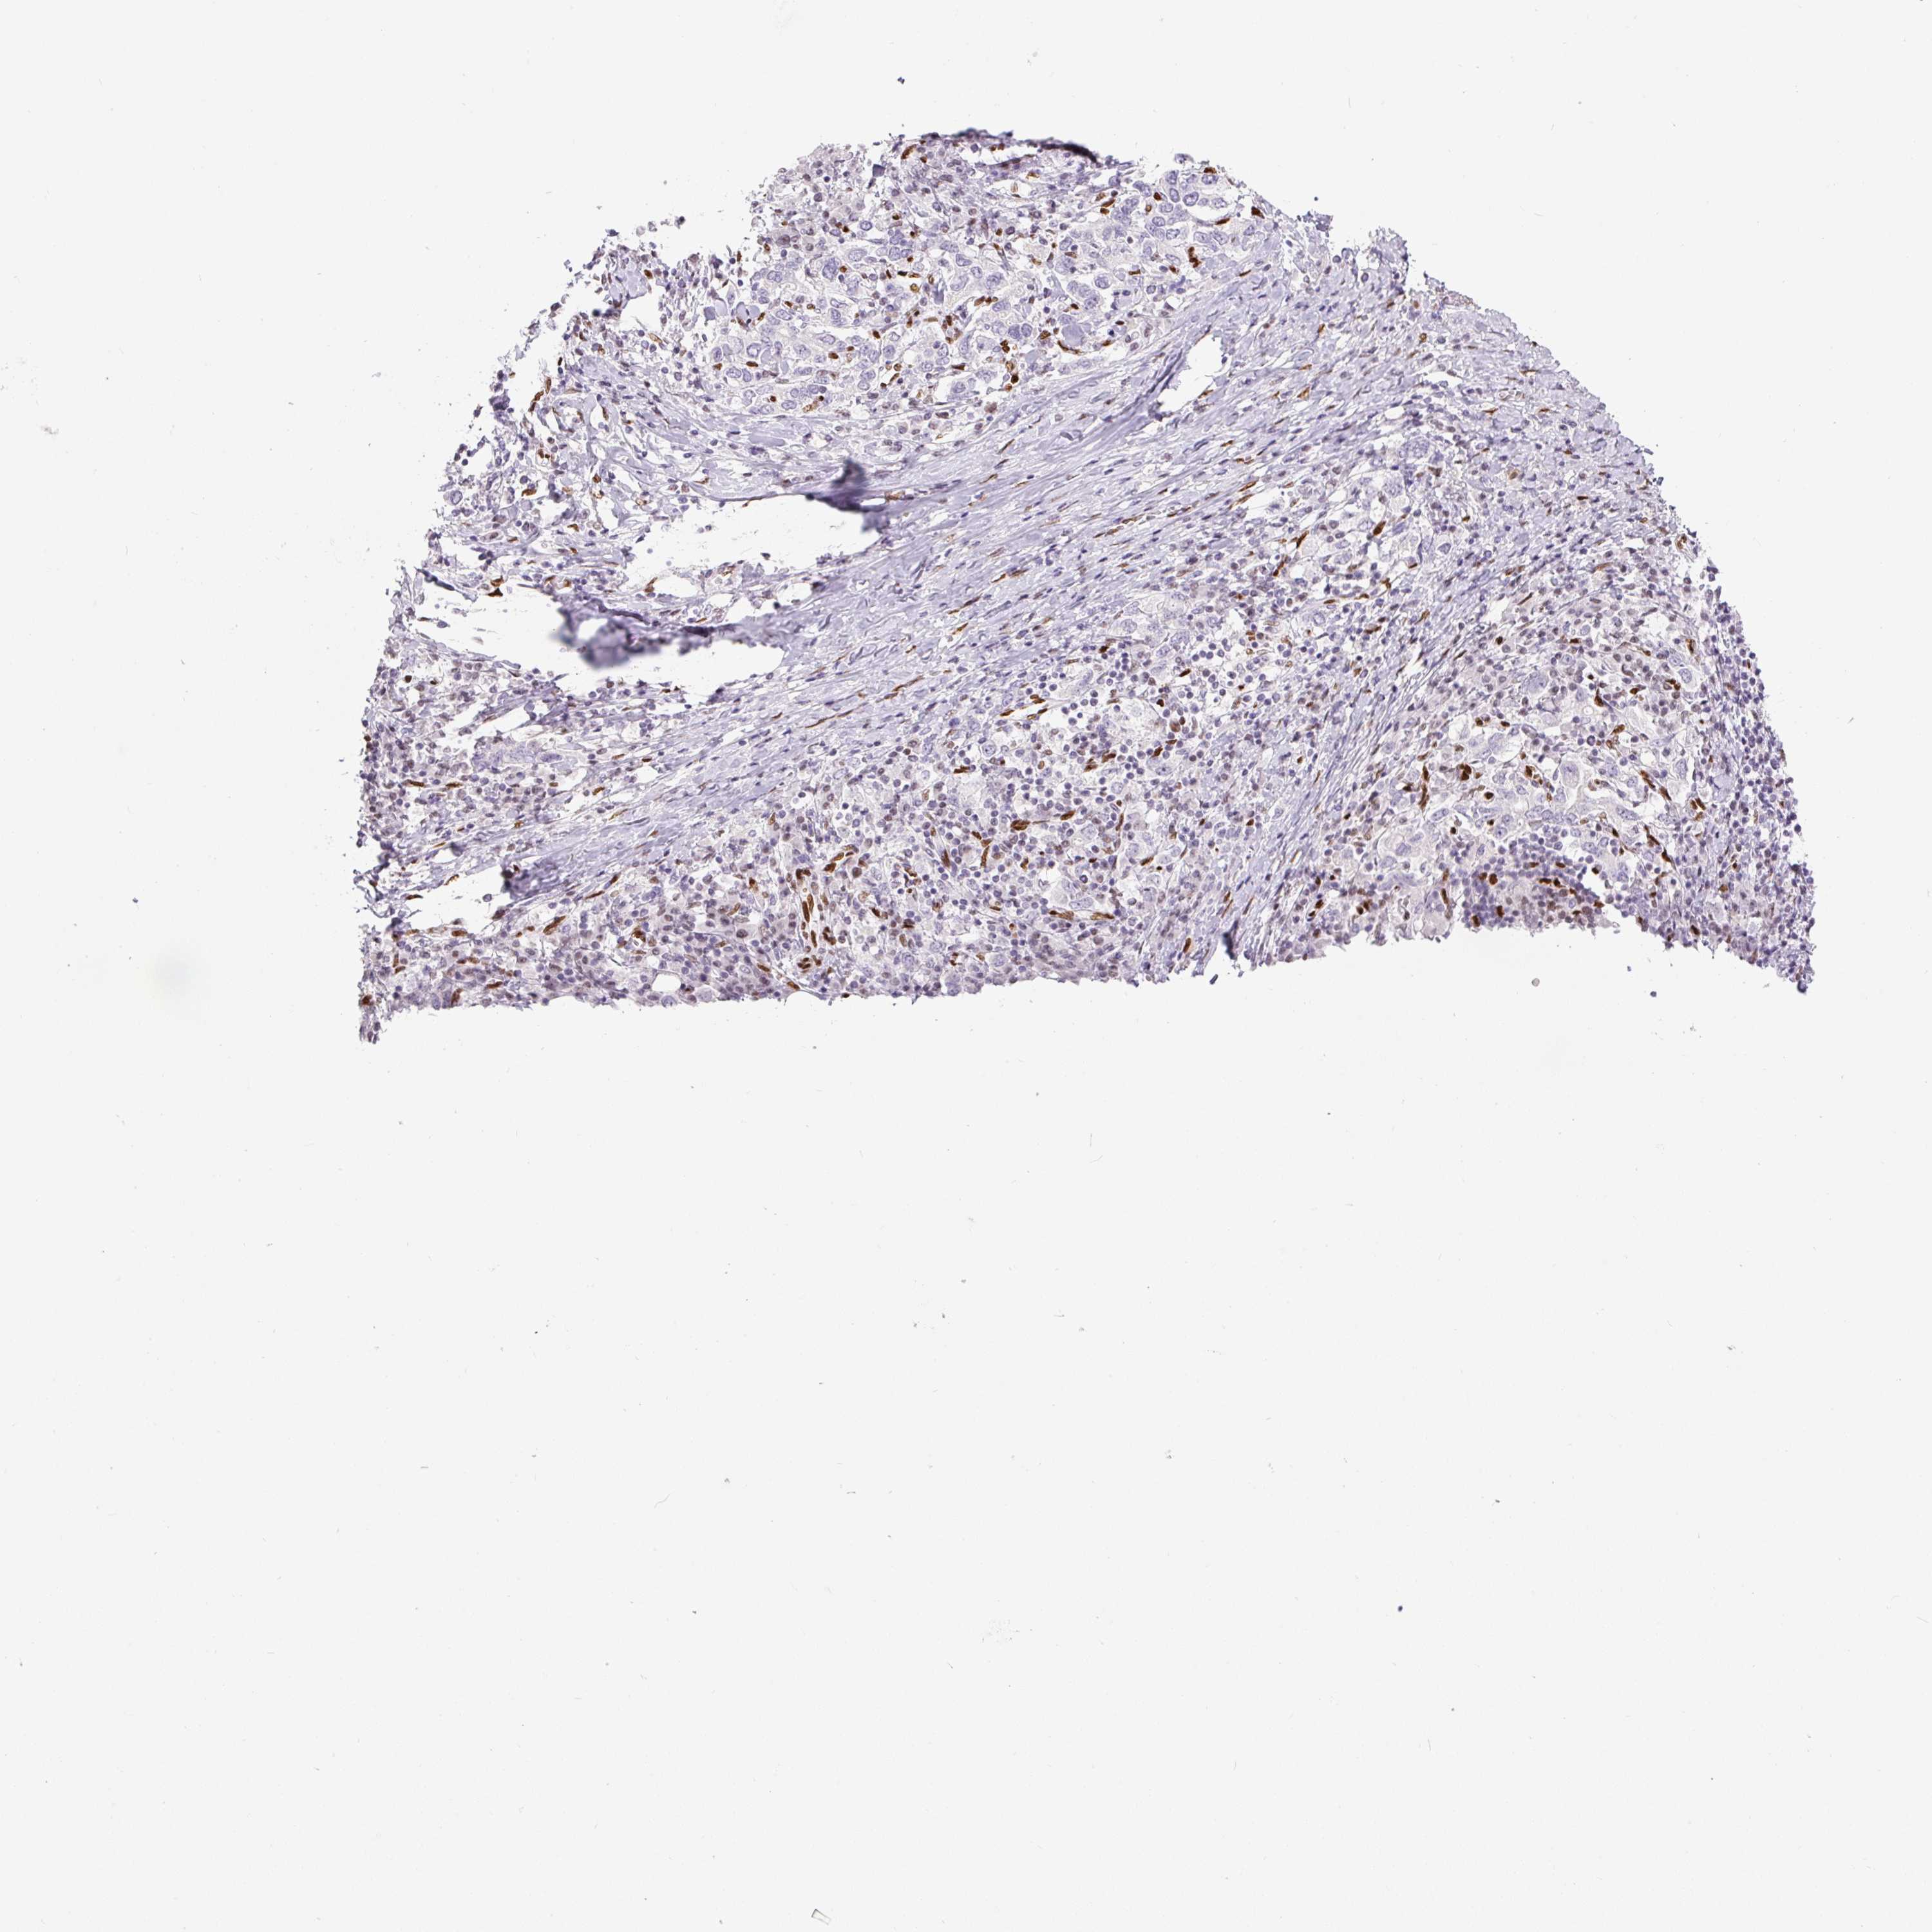

STOMACH CANCER - Protein expressioni

A mouse-over function shows sample information and annotation data. Click on an image to view it in a full screen mode. Samples can be filtered based on level of antibody staining by selecting one or several of the following categories: high, medium, low and not detected. The assay and annotation is described here.

Antibody stainingi

Antibody staining in the annotated cell types in the current human tissue is reported as not detected, low, medium, or high, based on conventional immunohistochemistry profiling in selected tissues. This score is based on the combination of the staining intensity and fraction of stained cells.

Each image is clickable and will lead to virtual microscopy that enables deeper exploration of all samples and also displays staining intensity scores, fraction scores and subcellular localization as well as patient and tissue information for each sample.

Antibody HPA027524

Antibody CAB058686

Antibody CAB079943

Staining

High

Medium

Low

Not detected

Intensity

Strong

Moderate

Weak

Negative

Quantity

>75%

75%-25%

<25%

None

Location

Nuclear

Cytoplasmic/membranous

Cytoplasmic/membranous,nuclear

Adenocarcinoma, NOS

Adenocarcinoma, High grade